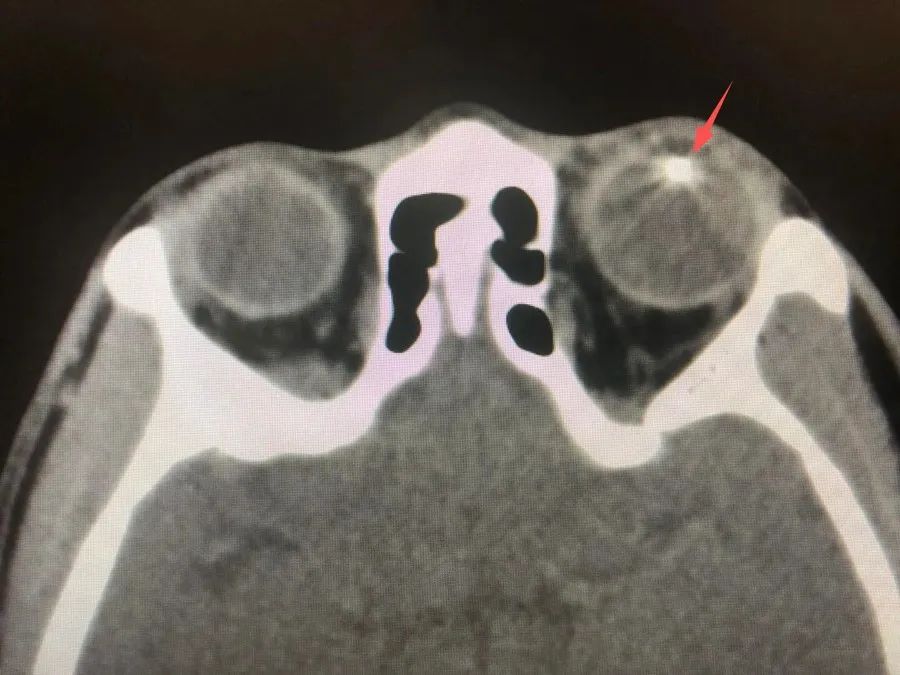

箭头所指金属异物位于左眼晶状体